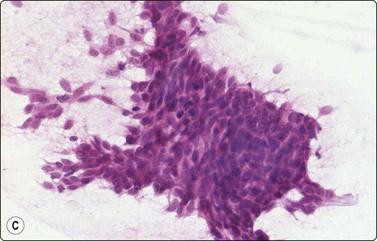

Basal cell carcinoma (Fig. 14.14)8,45-48

Criteria for diagnosis

Tight cell aggregates with sharp outline, smooth edges, often budding,

Palisading of nuclei along the edge of aggregates,

Small cells with scanty cyanophilic cytoplasm; indistinct cell borders,

Small, hyperchromatic, ovoid, overlapping nuclei; indistinct nucleoli,

Stromal material variable.

Most basal cell carcinomas (BCC) are diagnosed clinically. Scrape smears from the surface can provide rapid pretreatment confirmation, of particular importance if non-surgical treatment is considered. If the lesion is ulcerated, any inflammatory debris should be removed prior to vigorous scrapings.8 Non-ulcerated, deeply invasive tumors are suitable for FNB sampling using a thin 25–27-gauge needle.

The most characteristic feature of BCC in smears is the strong cohesiveness of the cells, which remain in well-defined tissue fragments of tightly packed small cells with palisading of nuclei along the edges. The fragments resemble tumor buds seen in tissue sections (Fig. 14.14A). The same pattern was seen in FNB smears from a rare case of distant metastasis to bone from of a large, deeply invasive BCC on the back of an elderly patient (Fig. 14.14B). The cells are small with very scanty cytoplasm and overlapping, ovoid, relatively uniform hyperchromatic nuclei. The chromatin is evenly distributed and nucleoli are inconspicuous. Subtyping of BCC is generally not possible, but stromal material can be prominent in smears from desmoplastic, infiltrating basal cell carcinoma, suggesting a differential diagnosis of chondroid syringoma (Fig. 14.14D).

image image image image

Fig. 14.14 Basal cell carcinoma

(A) Cohesive epithelial fragments with alternating sharp and irregular borders (H&E, IP); (B) Tissue fragments of very cohesive basaloid cells. The fragments have well-defined borders of cells with a tendency to palisading. This smear is a FNB sample from a bone deposit of metastasizing basal cell carcinoma (MGG, HP); (C) Tumor fragment of small, tightly packed cells, FNB smear (H&E, MP); (D) Basal cell carcinoma, infiltrating type; tumor fragment of closely packed small, uniform basal cells and adherent fibrillar fibrous stroma (MGG, LP).

In clinical practice, the main differential is BCC versus actinic keratosis. Christensen et al., in a study of 78 cases, found cytological diagnosis to be highly accurate if samples are adequate.48 In general, the microarchitecture and the predominance of typical basal cells are characteristic of BCC. Cells of actinic keratosis are less cohesive, and show features of dysplastic squamous epithelial cells with more abundant cytoplasm. Cells of non-keratinizing, basaloid squamous cell carcinoma are also less cohesive, larger, some with dense squamoid cytoplasm, some with prominent nucleoli.